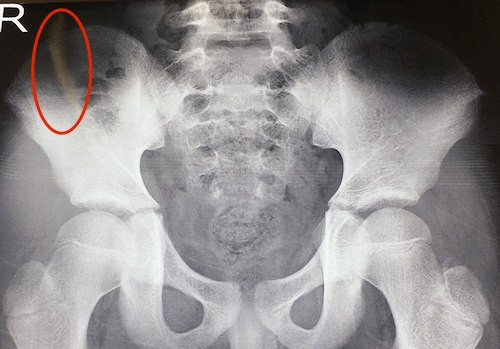

Bác sĩ Bệnh viện Chấn thương Chỉnh hình Nghệ An chỉ định bệnh nhi chụp X-quang, cộng hưởng từ và siêu âm. Kết quả phát hiện một dị vật hình dạng mờ nằm sâu trong vùng cơ mông của bé.

| Phim chụp X-quang cho thấy chiếc tăm (khoanh đỏ) đâm sâu trong mông bệnh nhi. |

Ngày 16/10, các bác sĩ tiến hành phẫu thuật rút dị vật cho bé. Mất hơn một giờ phẫu thuật, bác sĩ mới lấy được cây tăm nhọn dài 8 cm. Ước tính thời gian chiếc tăm nằm trong cơ thể cháu bé khoảng 10 đến 15 ngày.